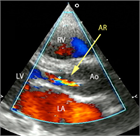

1. 心室中隔欠損は、欠損孔の部位により、膜性周囲部(perimembranous)、筋性部(muscular)、漏斗部または肺動脈弁下部(subarterial)に分類され、自然歴、手術適応が各々異なるため、部位診断は重要である。

1. 心室中隔欠損は自然閉鎖する場合もあるが、心不全症状を有する、あるいは肺高血圧を合併する場合、漏斗部欠損で大動脈弁の逆流を呈する場合は、外科手術の適応となる(推奨度1)。Eisenmenger症候群を呈すると手術適応がなくなるので、その前に適切な治療時期を逃さないことが大切である。